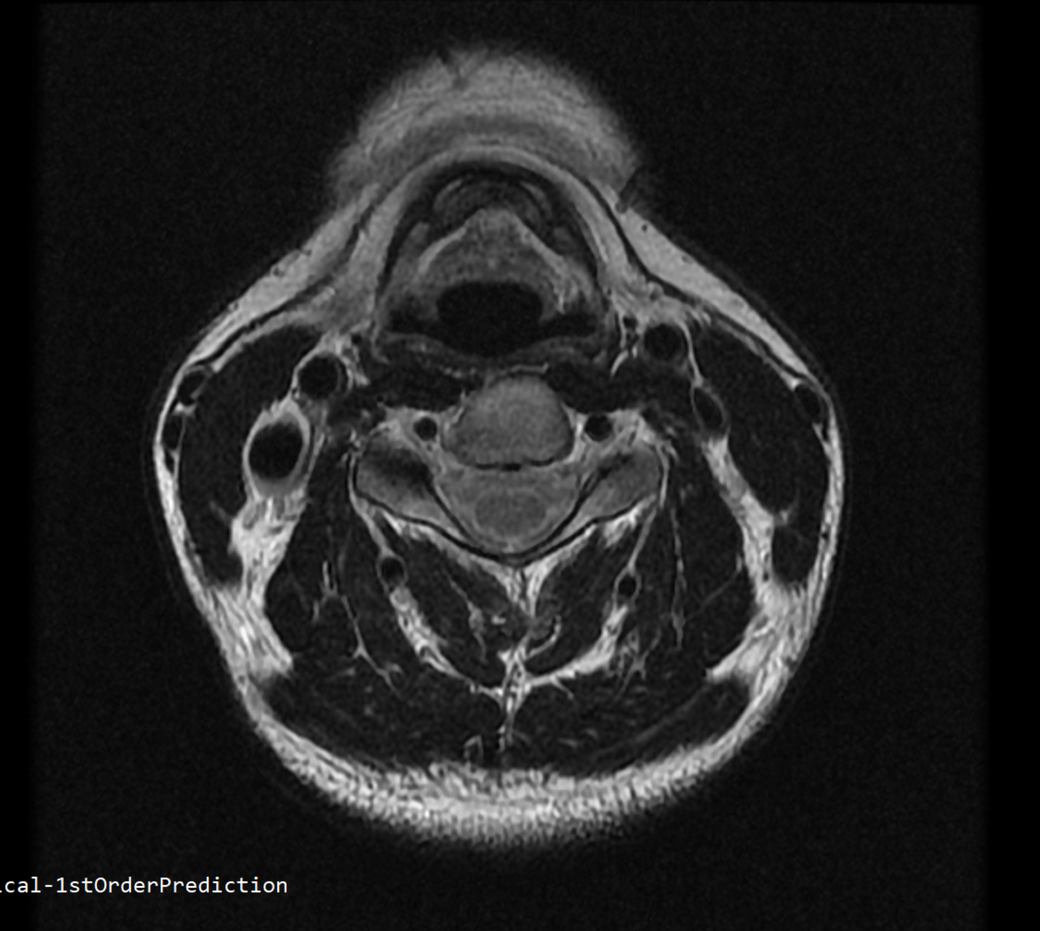

안녕하세요 목 경추 상단부터 순서대로 mri 촬영인데요

전체적으로 봐주시면 감사하겠습니다

• 1번 째 사진